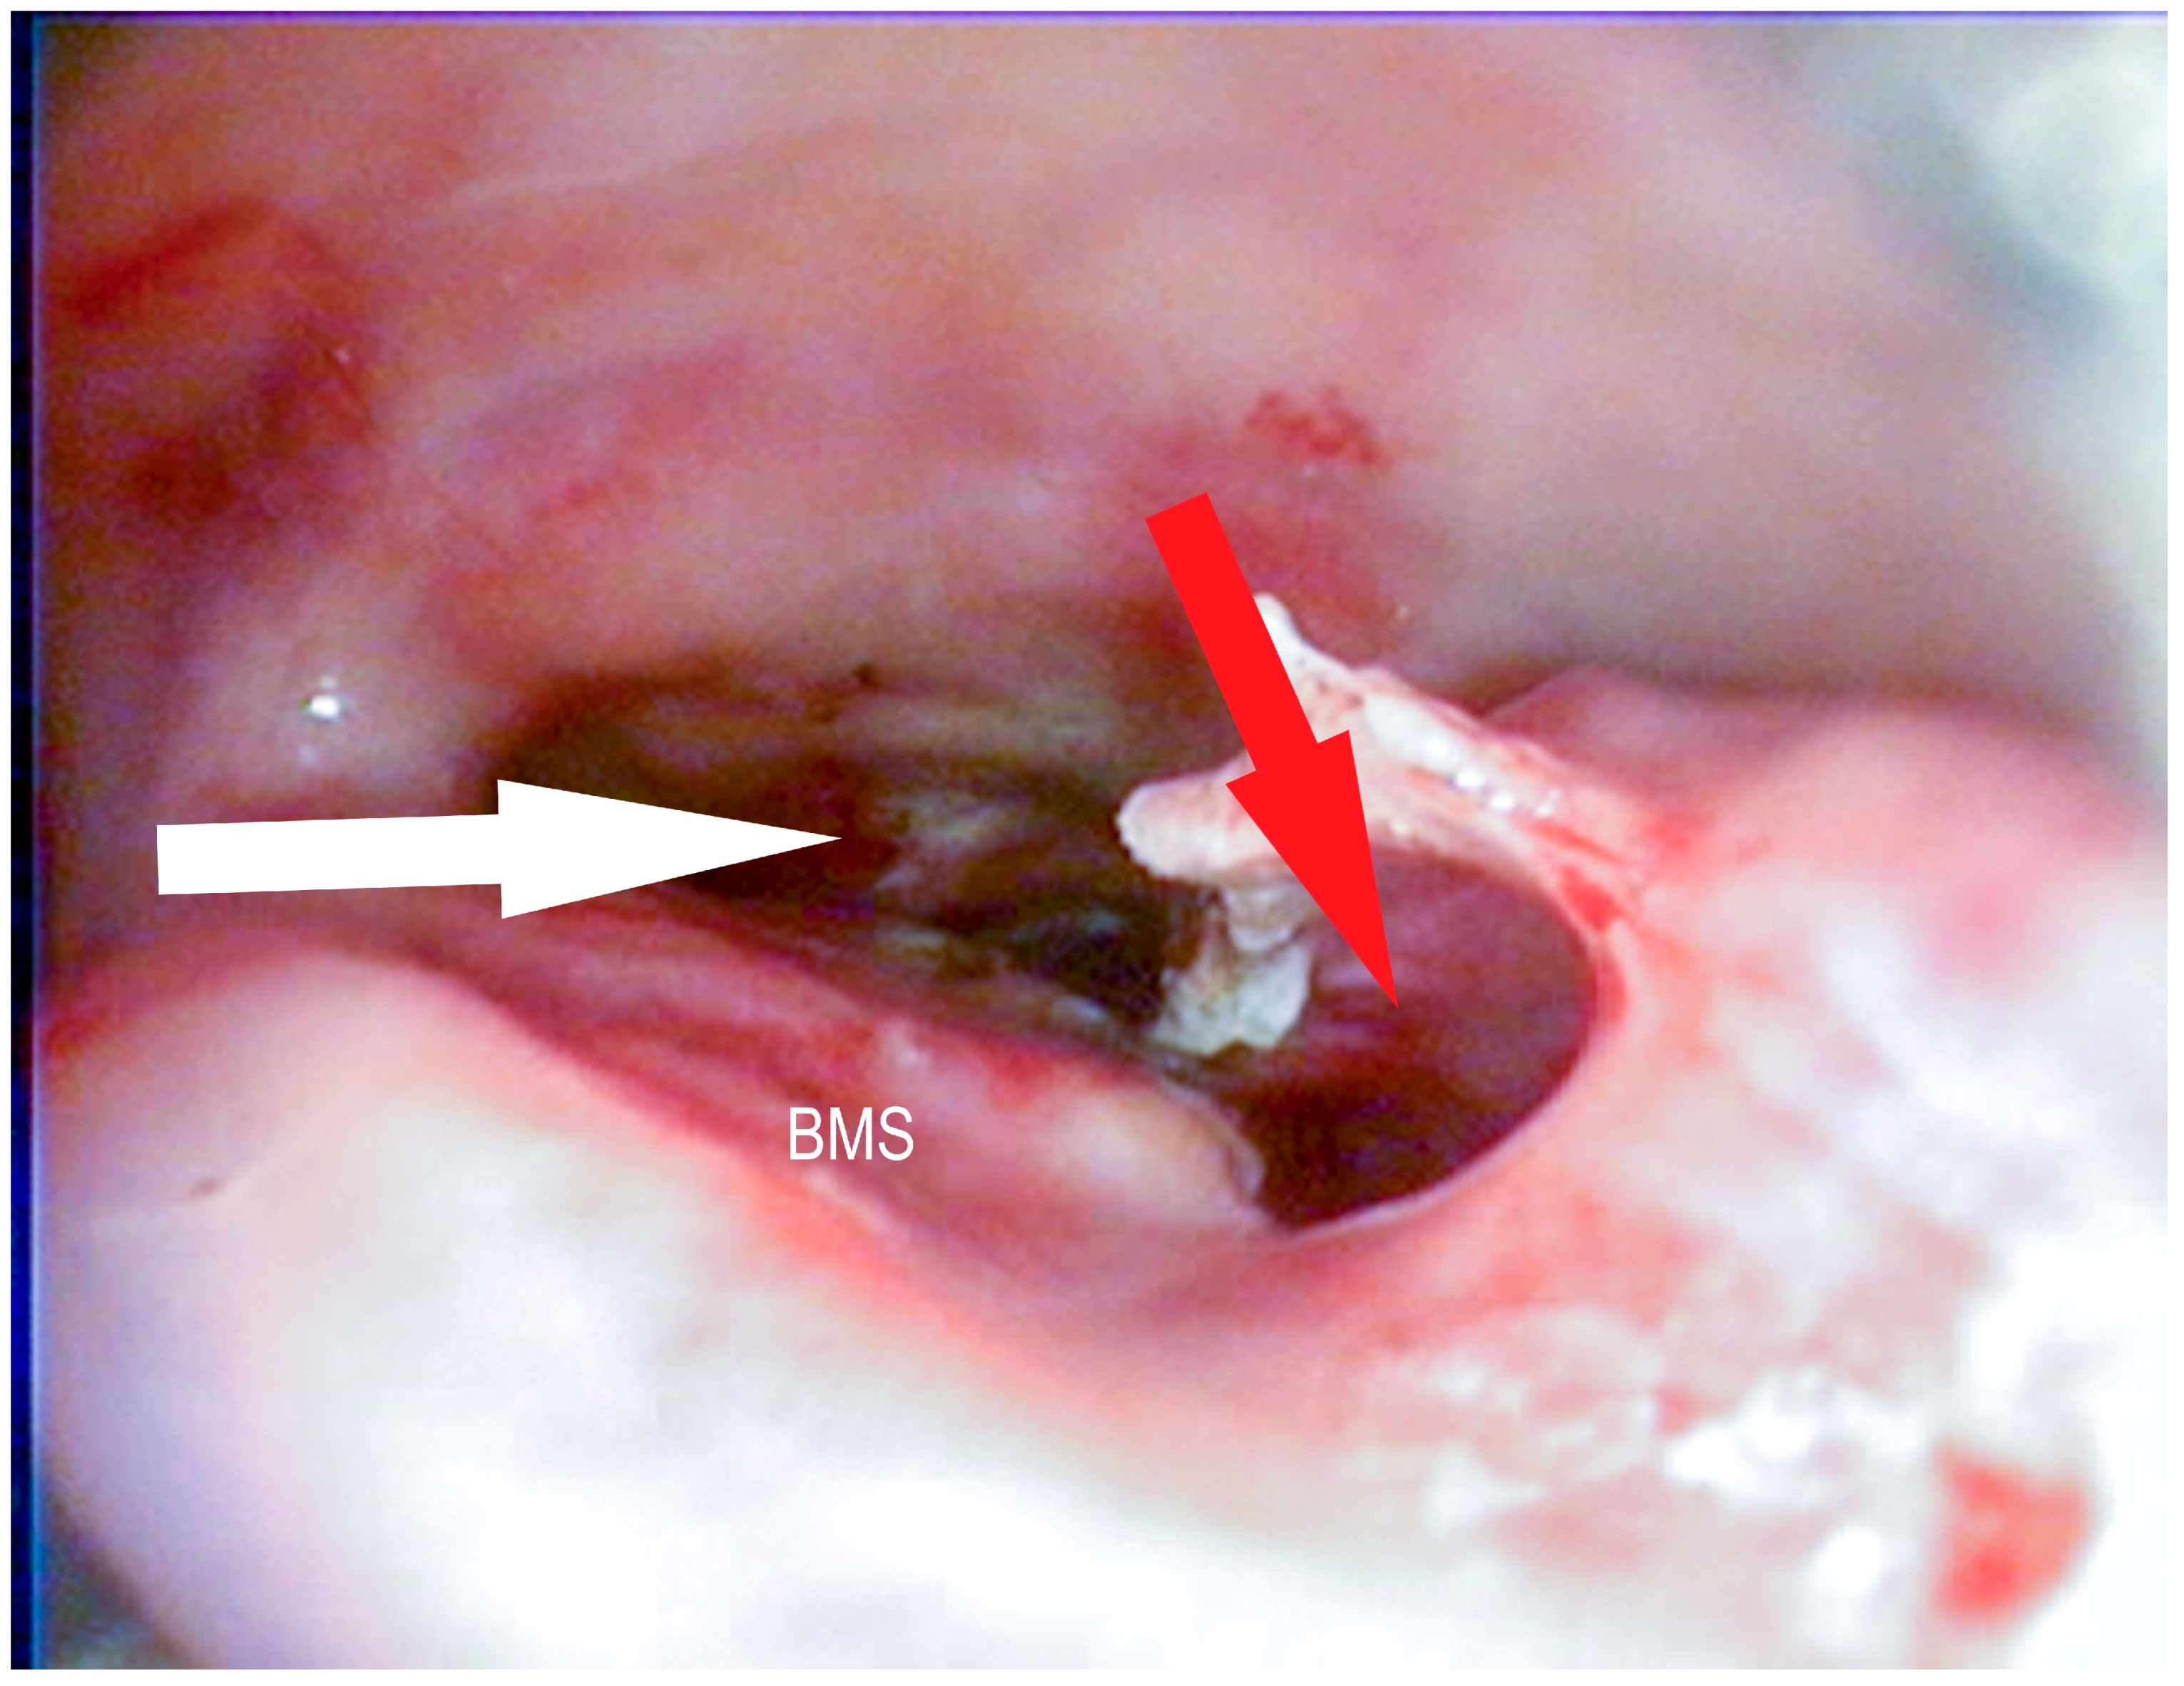

2.2.6. Transendoscopic Fenestration of the Bulla of the Maxillary Septum (BMS)

3.1.3. Conchotomy and Transendoscopic Laser Fenestration of the Bulla of the Maxillary Septum